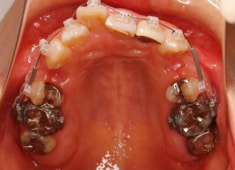

右下7番欠如歯(保存不可能歯につき抜歯)右下8番利用

治療法:フルパッシブブラケット:クリアスナップ

治療開始時